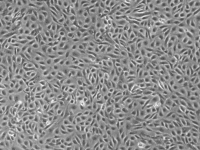

半贴壁半悬浮

2) 形态:半贴壁半悬浮